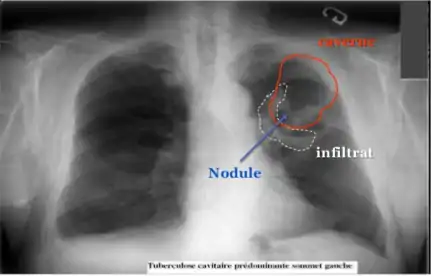

La modalité de diagnostic radiologique se révèle très utile et indiquée comme étant un examen de première intention en cas de tuberculose pulmonaire et ostéoarticulaire[77]. Cela est justifié par les images radiologiques plus ou moins spécifiques à la tuberculose. La littérature rapporte que la spécificité varie de 27 à 81 % selon l’étude. Les imageries idéales et révélatrices de la tuberculose répondent à certains attributs dont le premier est lié au siège. En raison de l’affinité que les BK ont envers les régions aérées, la lésion radiologique est souvent observée dans les parties hautes des poumons. Néanmoins, l’image radiographique peut contenir différentes formes :

• infiltrat : traduisant des lésions débutantes de l’infection via une opacité peu dense, hétérogène et étendue ;

• nodule : granulome de taille variable, isolé ou groupé ;

• tuberculome : nodule isolé pseudotumoral ;

• caverne : excavation par perte de substance au sein d’un infiltrat, aux parois épaisses.

Radialogie de la TBC.